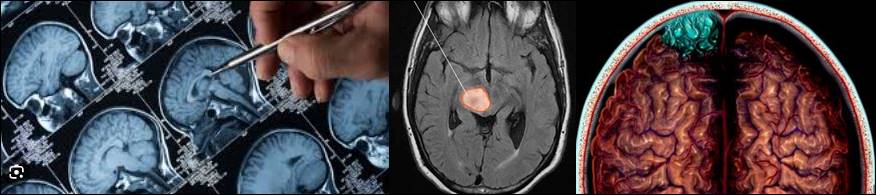

뇌종양 진단

뇌종양의 진단은 전문 의료진이 다양한 검사와 평가를 통해 수행됩니다. 주로 사용되는 진단 도구는 다음과 같습니다:

1. 뇌 영상 검사

① CT 스캔 (Computed Tomography): X선을 사용하여 뇌의 단면 이미지를 생성합니다. 뇌종양의 위치와 크기를 확인할 수 있습니다.

② MRI (Magnetic Resonance Imaging): 자기장과 라디오 파형을 사용하여 뇌의 상세한 이미지를 제공합니다. 뇌종양의 종류와 특성을 더 자세히 파악할 수 있습니다.